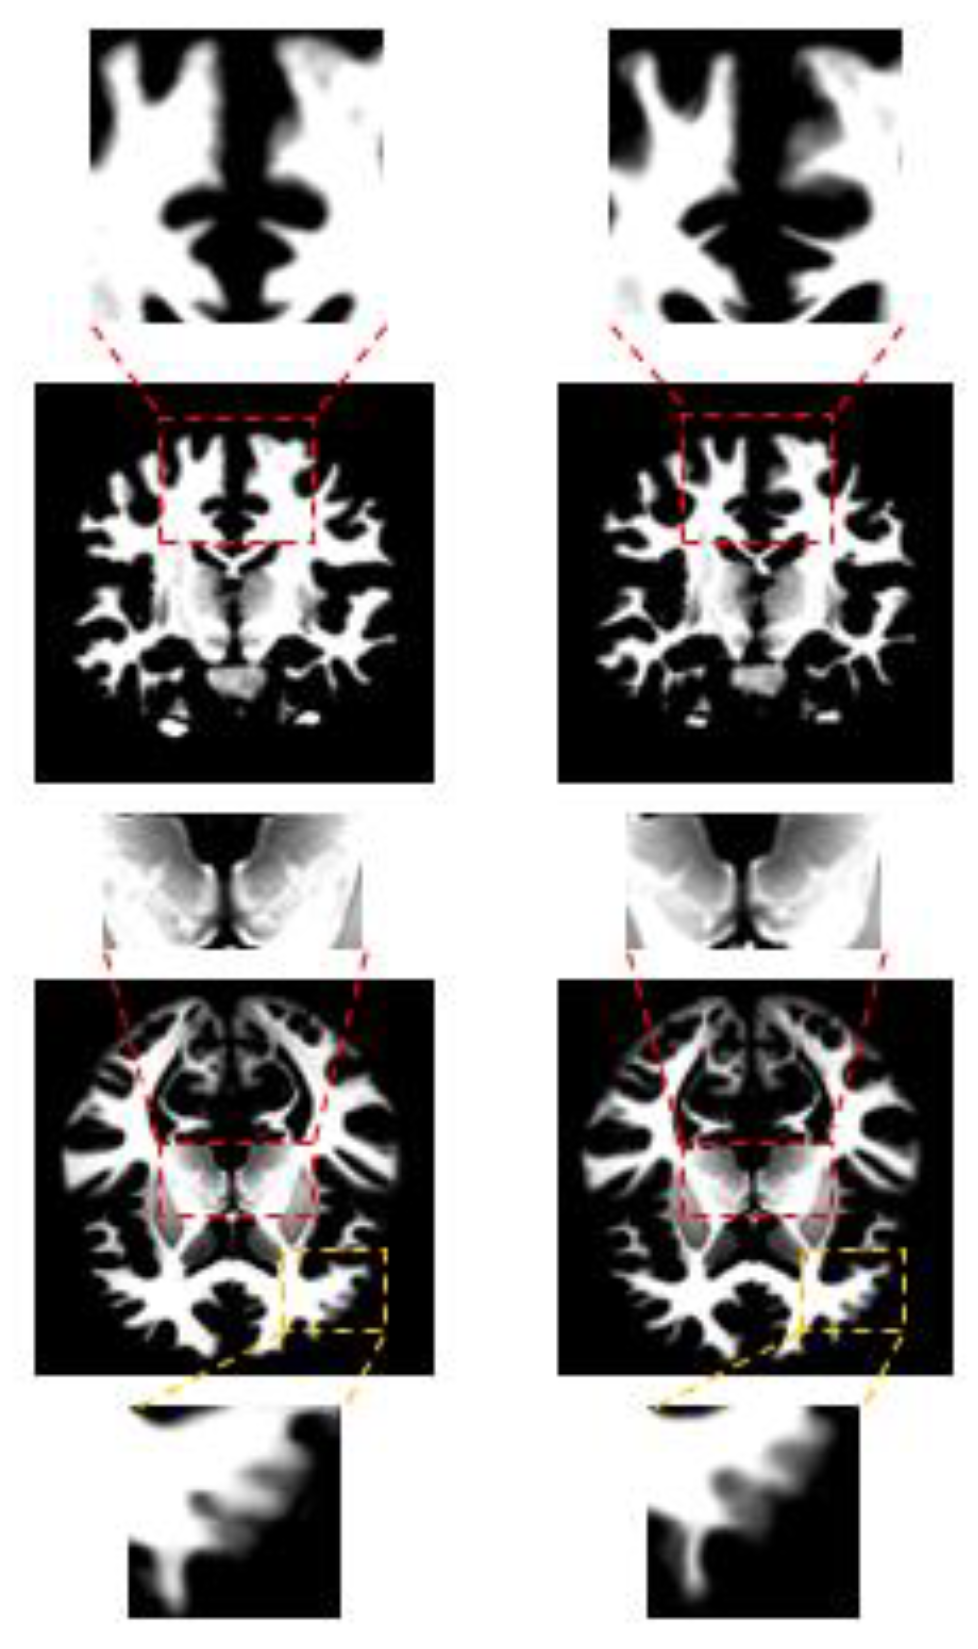

5.1. Border Enhancement Experiment